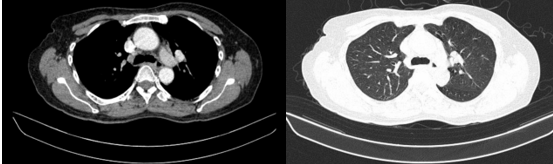

Chụp cắt lớp vi tính bụng – tiểu khung: Hình ảnh giãn đường mật trong gan phải/ Sonde dẫn lưu đường mật gan phải- Gan trái đã cắt.

Hình 7. Phim chụp cắt lớp vi tính vụng cho thấy phần gan trái đã cắt (hình mũi tên)- Sonde dẫn lưu đường mật gan phải( vòng tròn đỏ).